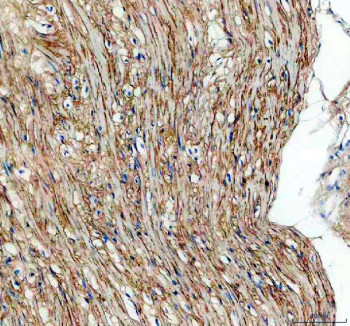

Adding 0.2 ml of distilled water will yield a concentration of 500 ug/ml. The TGFBI antibody targets Transforming growth factor-beta-induced protein ig-h3, a secreted extracellular matrix protein encoded by the TGFBI gene. Induced by TGF-beta signaling, this protein plays critical roles in cell adhesion, migration, and matrix organization. Transforming growth factor-beta-induced protein ig-h3 contains multiple fasciclin domains that mediate interactions with integrins and collagen, promoting tissue integrity and repair. The TGFBI antibody provides a valuable tool for studying extracellular signaling, wound healing, and fibrotic disease mechanisms.Transforming growth factor-beta-induced protein ig-h3 is secreted into the extracellular space, where it binds integrins such as alphavbeta3 and alpha3beta1 to regulate adhesion and cell-matrix communication. It is widely expressed in corneal, epithelial, and connective tissues. The TGFBI antibody allows visualization of its distribution and quantification under TGF-beta stimulation, providing insight into how this protein orchestrates matrix remodeling. Its RGD motif facilitates integrin binding, influencing cell attachment, migration, and differentiation.Mutations in the TGFBI gene cause a spectrum of hereditary corneal dystrophies, including granular, lattice, and Avellino types, characterized by amyloid or hyaline deposits in the cornea. The TGFBI antibody supports studies into these pathologies, enabling detection of protein accumulation and abnormal deposition patterns. By tracking misfolded Transforming growth factor-beta-induced protein ig-h3, researchers can better understand disease progression and potential therapeutic interventions aimed at preventing protein aggregation.Beyond ocular disease, TGFBI is implicated in cancer, fibrosis, and tissue regeneration. It may function as either a tumor suppressor or promoter depending on context, influencing epithelial-to-mesenchymal transition (EMT) and extracellular matrix stiffness. The TGFBI antibody supports exploration of these dual roles by enabling quantification of expression levels in tumor microenvironments and fibrotic tissues. TGFBI overexpression is associated with enhanced metastasis in certain cancers, making it a potential biomarker for disease progression.The TGFBI antibody performs well in western blotting, immunohistochemistry, and immunofluorescence, showing distinct extracellular and pericellular staining consistent with matrix localization. NSJ Bioreagents provides this antibody as a validated reagent with reproducible specificity across model systems. By supporting detailed study of Transforming growth factor-beta-induced protein ig-h3, the TGFBI antibody advances understanding of matrix biology, TGF-beta signaling, and the molecular mechanisms driving fibrosis and corneal dystrophy.